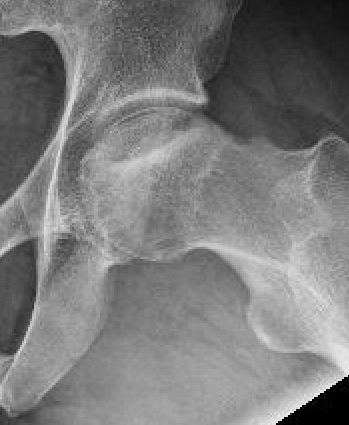

Technique

- AP and lateral xray

- entry point through greater trochanter

- above lesser trochanter to reduce fracture risk

- enter site of AVN

- overdrill

- +/- bone graft / vascularized bone graft / tantalum rod / BMAC (bone marrow aspirate concentrate)